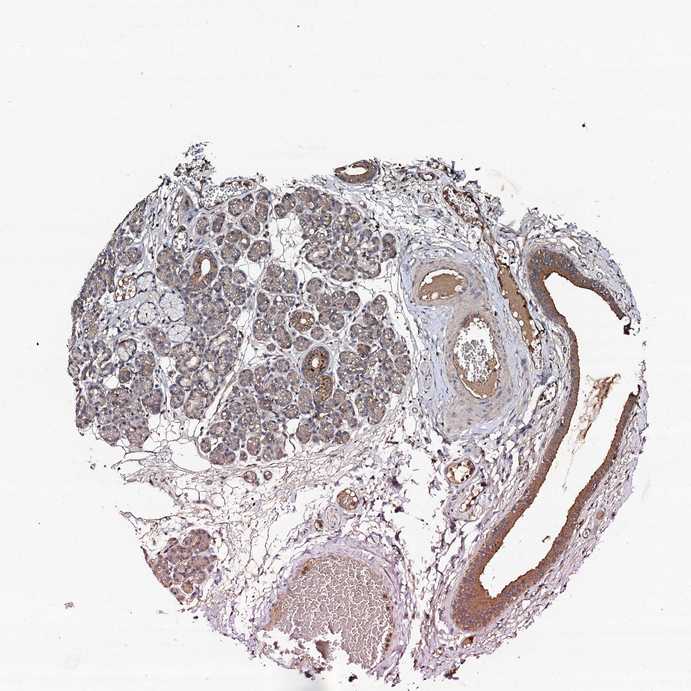

SALIVARY GLAND - Antibody stainingi

Antibody staining in the annotated cell types in the current human tissue is reported as not detected, low, medium, or high, based on conventional immunohistochemistry profiling in selected tissues. This score is based on the combination of the staining intensity and fraction of stained cells.

Each image is clickable and will lead to virtual microscopy that enables deeper exploration of all samples and also displays staining intensity scores, fraction scores and subcellular localization as well as patient and tissue information for each sample.

Antibody HPA039321

Glandular cells Low